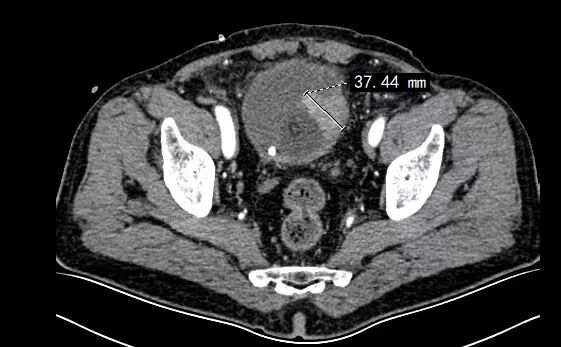

今年3月,69岁的王老太(化姓)经常尿频、尿急、尿痛。本以为是尿道炎,但吃了消炎药症状缓解并不明显,便前往十堰市人民医院泌尿外科就诊。经过膀胱镜及病理检查,发现她膀胱壁有一约3公分的肿瘤,且浸润至膀胱肌层。

▲王老太膀胱壁约3公分的肿瘤

在详细评估了王老太的身体状况后,李云飞专门为她制定了精细的手术方案,腹腔镜下全膀胱根治性切除术+原位新膀胱术。手术截取约45厘米末端回肠,将其重建呈接近球形制做成新膀胱。目前患者已经顺利康复出院,术后不用带尿袋,生活质量接近正常。